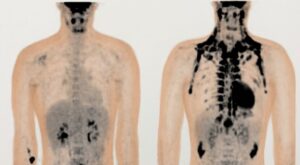

Fisiopatología del Tejido Adiposo

Obesidad del Adulto